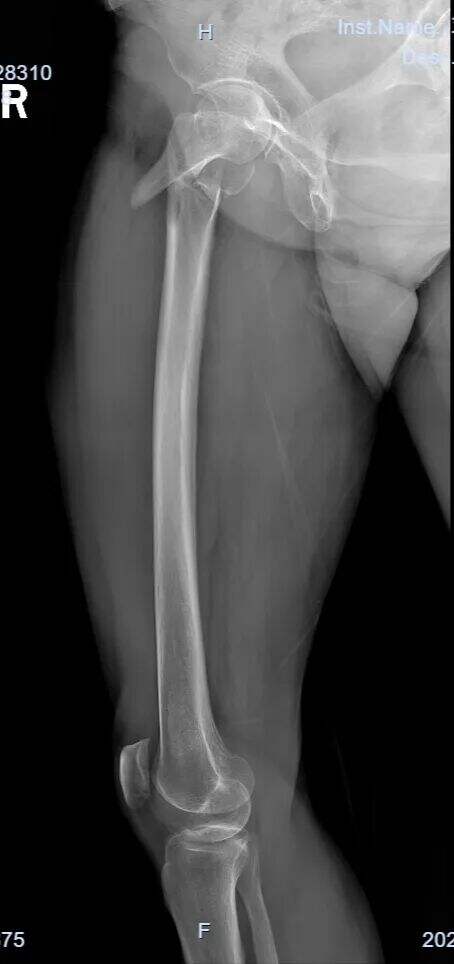

Starejša ženska, sprejeta po padcu.

Diagnoza: Pravi femoralni intertrohanterni zlom (AO razvrstitev tipa 31-A1.3).

Pri zlomih tipa 31-A1.3 je doseganje zadovoljive zmanjšanja vedno bilo izziv.